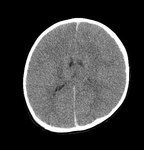

MRI depicting subdural hygromas surrounding severe brain atrophy from abusive head trauma. This child was initially erroneously diagnosed with meningitis

From the personal collection of Alice Newton, MD; used with permission